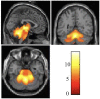

Background: Spinocerebellar ataxia type 3/Machado-Joseph disease (SCA3/MJD) is one of the nine polyglutamine (polyQ) diseases and is caused by a CAG repeat expansion within the coding sequence of the ATXN3 gene. Few multimodal imaging analyses of the macro- and micro-structural changes have been performed. Methods: In the present study, we recruited 31 genetically-confirmed symptomatic SCA3/MJD patients and 31 healthy subjects as controls for a multimodal neuroimaging study using structural magnetic resonance imaging (sMRI), proton magnetic resonance spectroscopy (1H-MRS) and diffusion tensor imaging (DTI). Results: The SCA3/MJD patients displayed a significantly reduced of gray matter volume in the cerebellum, pons, midbrain and medulla, as well as inferior frontal gyrus and insula, and left superior frontal gyrus. The total International Cooperative Ataxia Rating Scale (ICARS) score was inversely correlated with the gray matter volume in the cerebellar culmen, pons and midbrain. The numbers of CAG repeats in the expanded alleles were inversely correlated with the gray matter in the cerebellar culmen. NAA/Cr and NAA/Cho ratio in the middle cerebellar peduncles, dentate nucleus, cerebellar vermis, and thalamus in the SCA3/MJD patients were significantly reduced when compared to that in the normal controls, suggesting neurochemical alterations in cerebellum in the SCA3/MJD patients. Tract-Based Spatial Statistics (TBSS) analysis revealed significant lower volume and mean FA values of the cerebellar peduncles, which inversely correlated with the total scores of ICARS in our patients. Conclusions: In this study, we demonstrated cerebellar degeneration in SCA3/MJD based on tissue volume, neurochemistry, and tissue microstructure. Moreover, the associations between the clinical measures, cerebellar degeneration and genetic variation support a distinct genotype-phenotype relationship in SCA3/MJD.